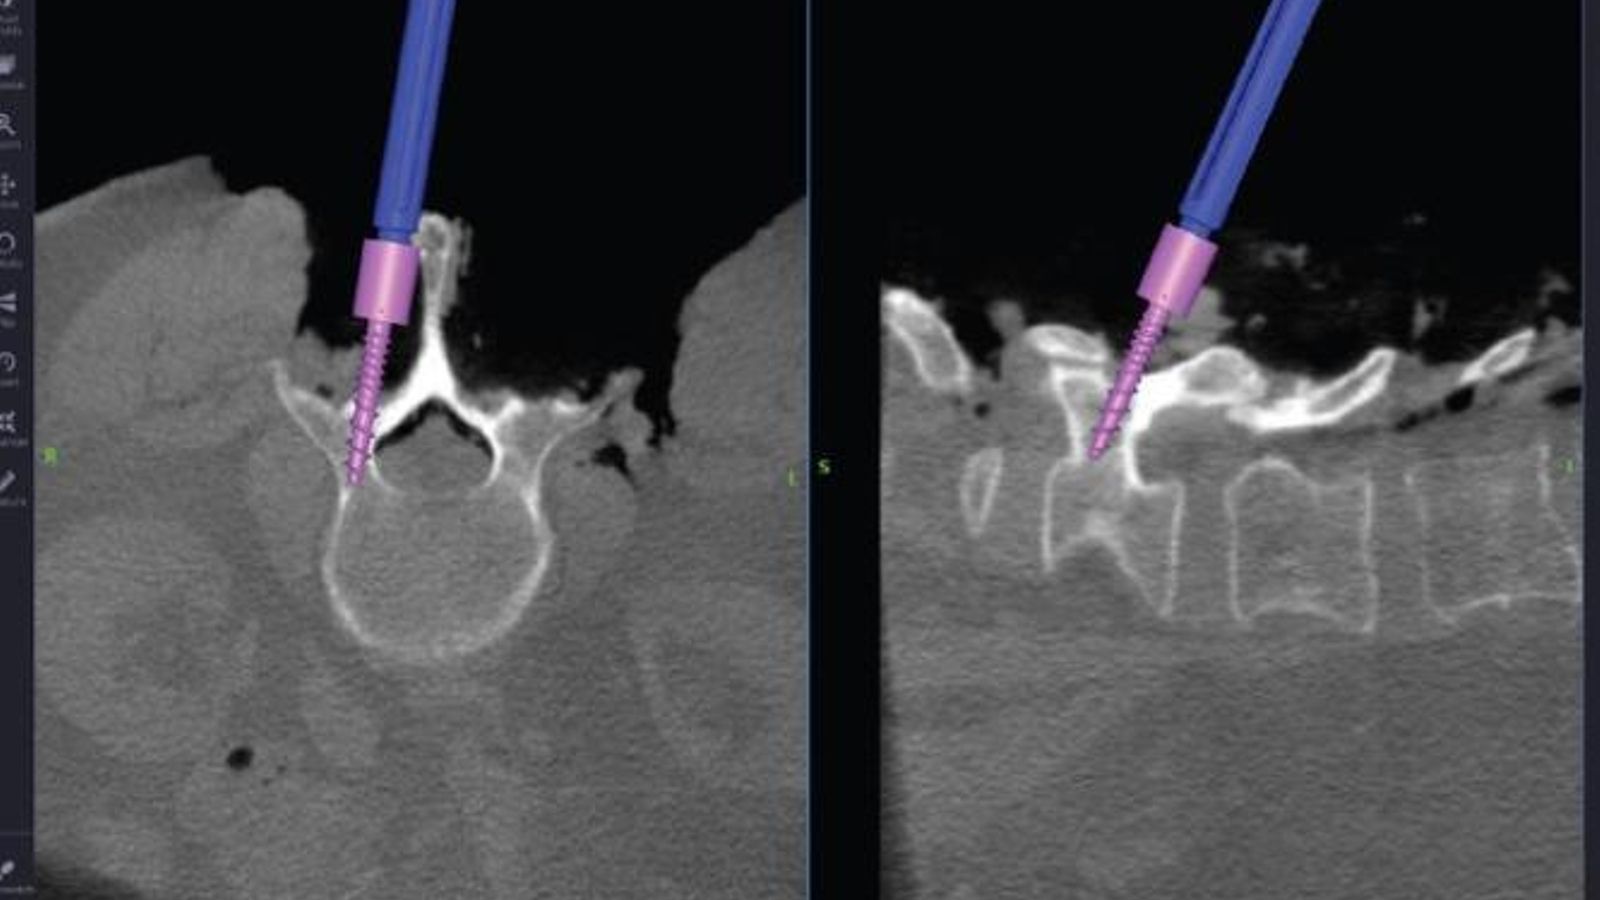

Vithas Granada realiza neurocirugía craneal y espinal avanzada con neuronavegación de última generación

El Hospital Vithas Granada ha adquirido un neuronavegador de última generación con módulo espinal que ayudará a los cirujanos a realizar intervenciones vertebrales a cualquier nivel con la mayor seguridad y eficacia.

Vithas Granada, que ya dispone de los últimos adelantos técnicos para realizar la cirugía craneal y espinal de forma segura y eficaz y con el equipo humano especializado necesario para ello, da un paso más con la adquisición de este neuronavegador, que viene a completar la unidad de neurocirugía que cuenta con técnicas de neurofisiología intraoperatoria y con el microscopio operatorio dotado de luz infrarroja y ultravioleta para cirugía vascular y tumoral.

El uso del microscopio operatorio con la magnificación e iluminación que proporciona, permite cirugías en zonas profundas del cerebro a través de pequeñas aberturas. El uso de técnicas de fluorescencia asociadas al microscopio mejora la resección de tumores o aportan seguridad en el manejo de los problemas vasculares. La monitorización neurofisiológica intraoperatoria constituye una herramienta indispensable en el manejo de problemas que asientan en áreas elocuentes, y la neuronavegación permite al cirujano la localización de estructuras internas antes de realizar la incisión.

El equipo de Neurocirugía del Hospital Vithas, formado por los doctores Horcajadas, Jorques y Román (Neurosalus21) ha apostado siempre por una atención integral de sus pacientes y por minimizar la agresión de las técnicas quirúrgicas, incorporando en su cartera de servicios técnicas mínimamente invasivas, por lo que se han mostrado muy satisfechos con la adquisición de este equipo, el S8 de Medtronic, que es un navegador de última generación que dispone de todas estas herramientas y que va a suponer un salto de calidad en la atención de los pacientes con patología neuroquirúrgica en el Hospital Vithas, convirtiéndolo en el primer centro privado andaluz que dispone de navegación espinal.